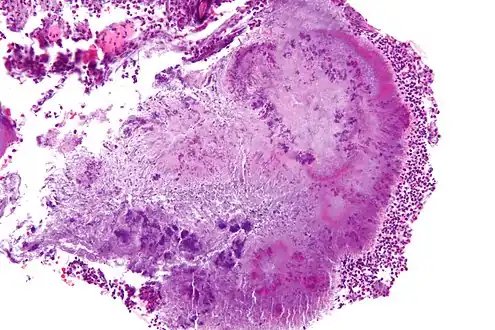

Micrograph of actinomycosis, H&E stain